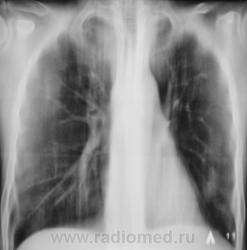

Контроль после флюорографии.